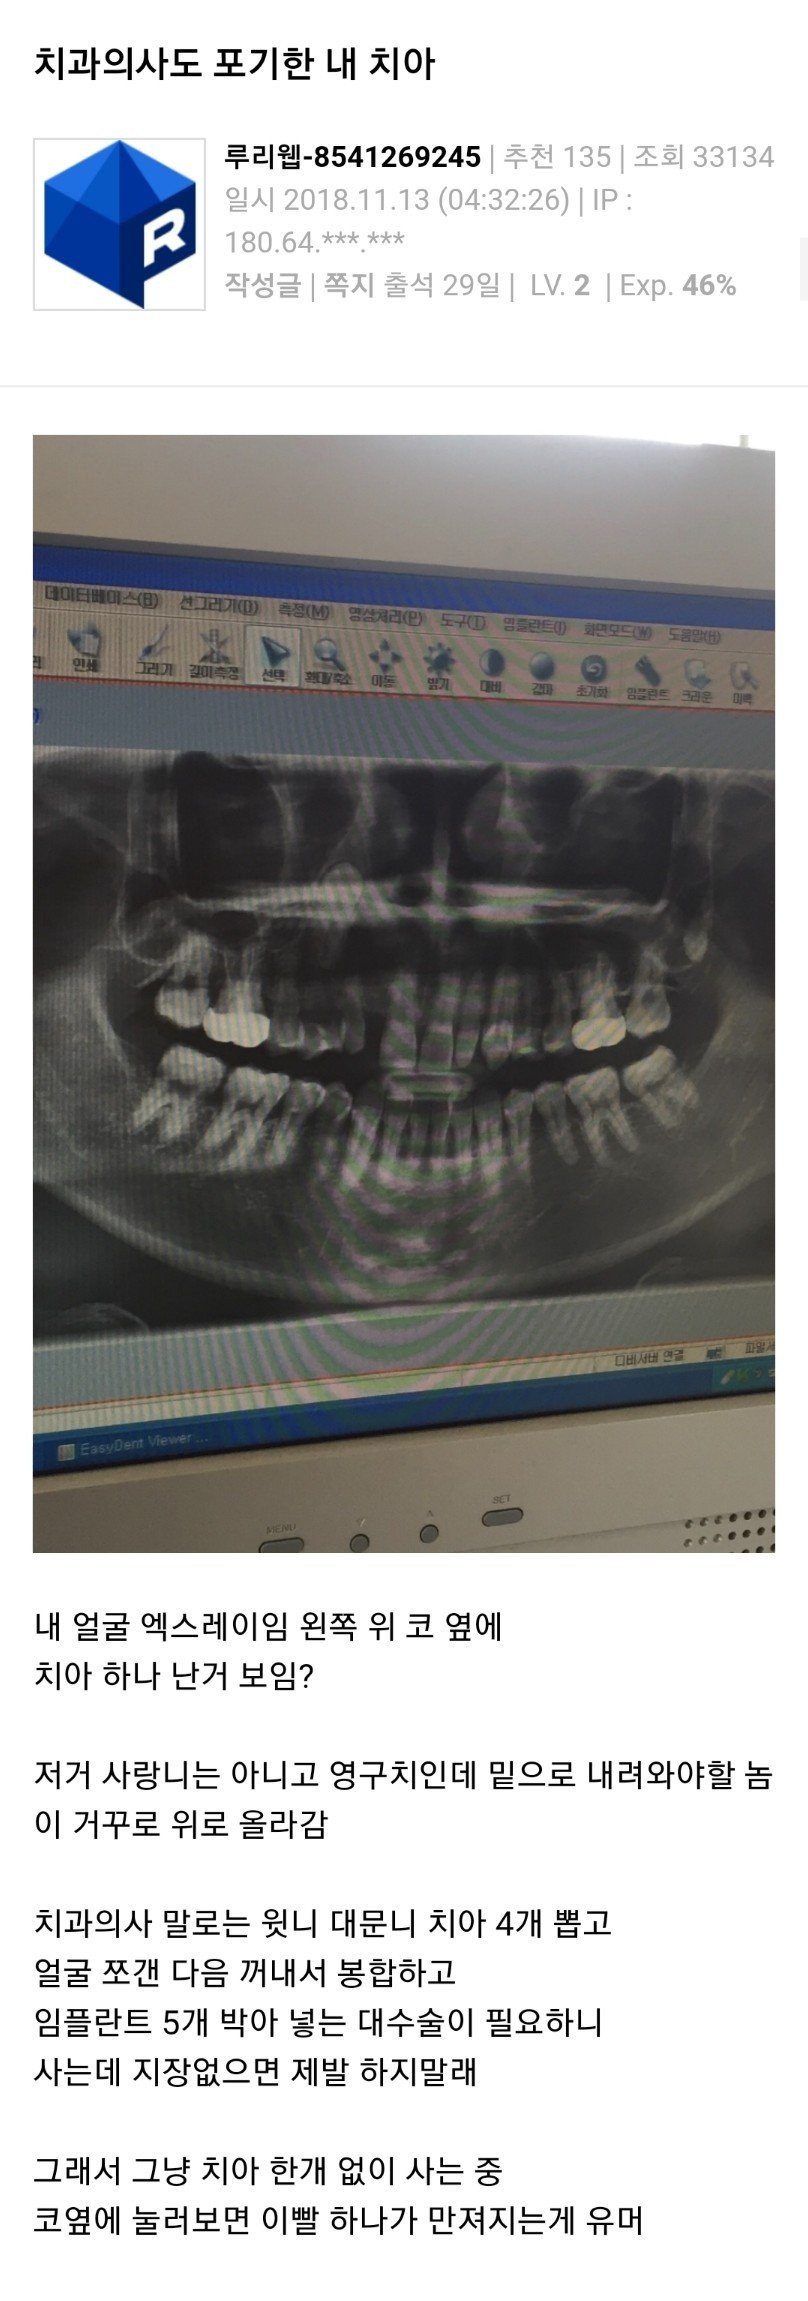

의사도 포기한 사랑니